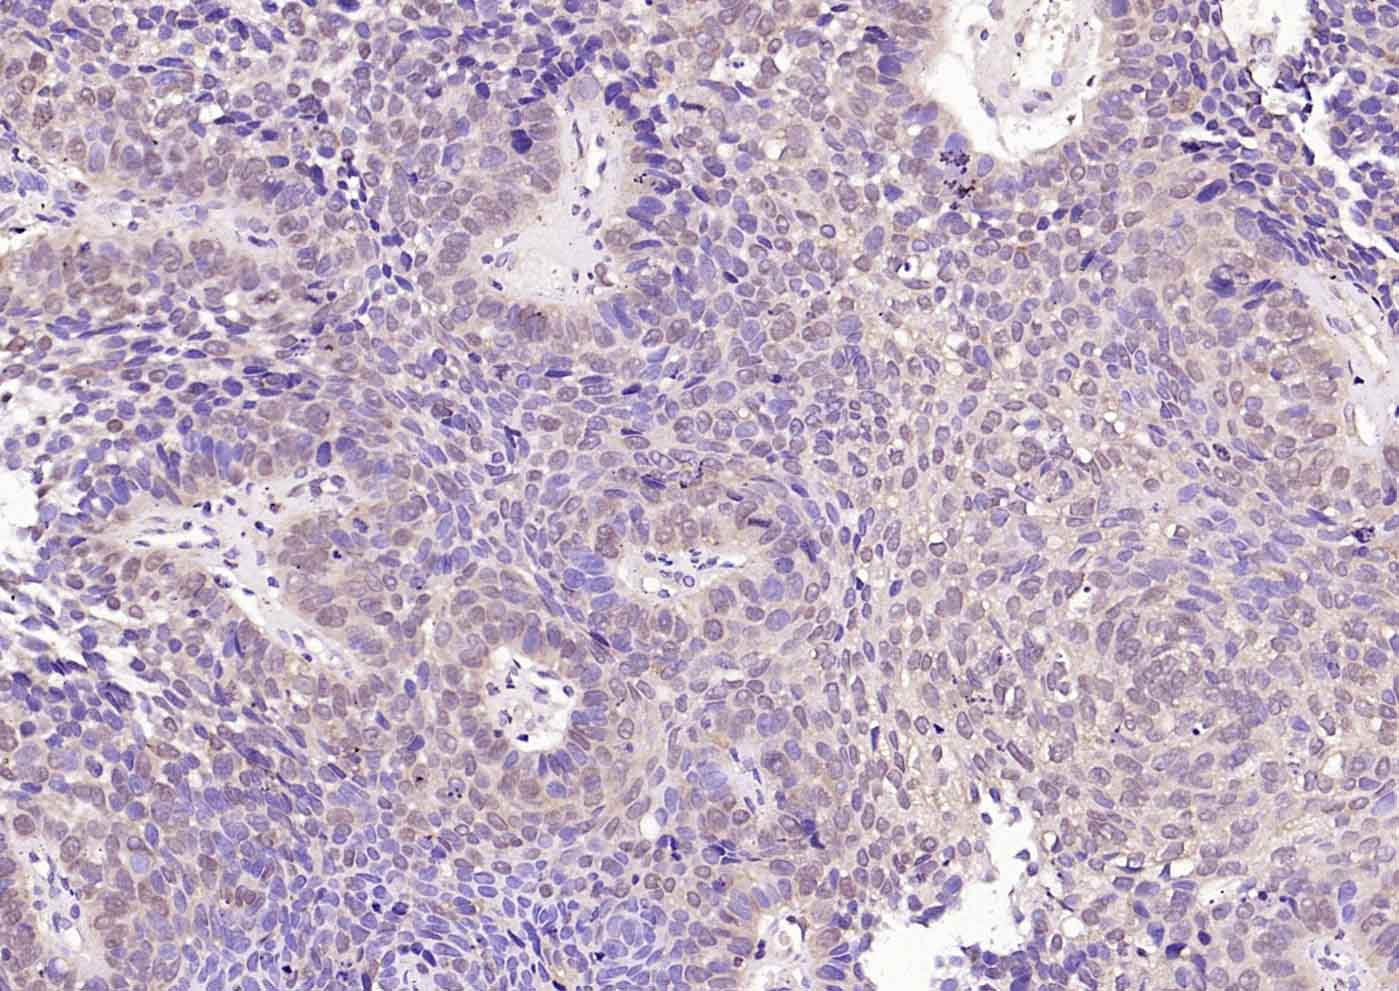

Paraformaldehyde-fixed, paraffin embedded (human breast carcinoma); Antigen retrieval by boiling in sodium citrate buffer (pH6.0) for 15min; Block endogenous peroxidase by 3% hydrogen peroxide for 20 minutes; Blocking buffer (normal goat serum) at 37°C for 30min; Incubation with (VEGFR3) Polyclonal Antibody, Unconjugated (bs-24954R) at 1:200 overnight at 4°C, followed by operating according to SP Kit(Rabbit) (sp-0023) instructionsand DAB staining.